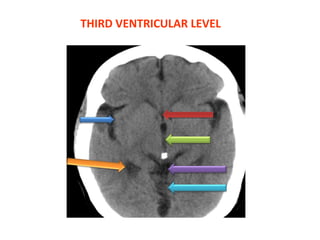

THIRD VENTRICULAR LEVEL

• 14.